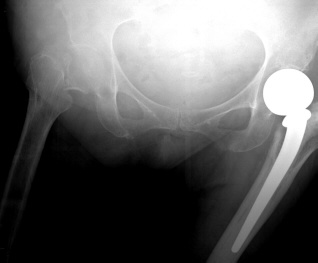

Giriraj orthopedic trauma surgeons offer treatment for these unplanned, critical events - major and minor fractures, nerve and tendon injuries, joint dislocation and other orthopedic injuries. Our surgeons provide expert, compassionate care for patients and their families in these emergencies, beginning with new, less invasive techniques for highly specialized reconstructive surgeries. As a Level One Trauma Center, Giriraj Hospital provides the highest level of emergency care in with state-of-the-art facilities and services. Our orthopedic surgeons are fellowship-trained and experts in orthopedic surgery, so our patients receive highly specialized emergency and follow-up care.

Additionally, Giriraj Hospital's high-tech imaging and surgical equipment can give patients and families choices in their treatment or therapy. For example, depending on the injury, patients may have surgical, medicinal or therapeutic options - or a combination of all three types of therapy. Our experienced Giriraj Hospital trauma team to provide comprehensive care to acutely injured patients. This multidisciplinary team includes general surgery trauma surgeons, nursing staff, mid-level providers and therapists.